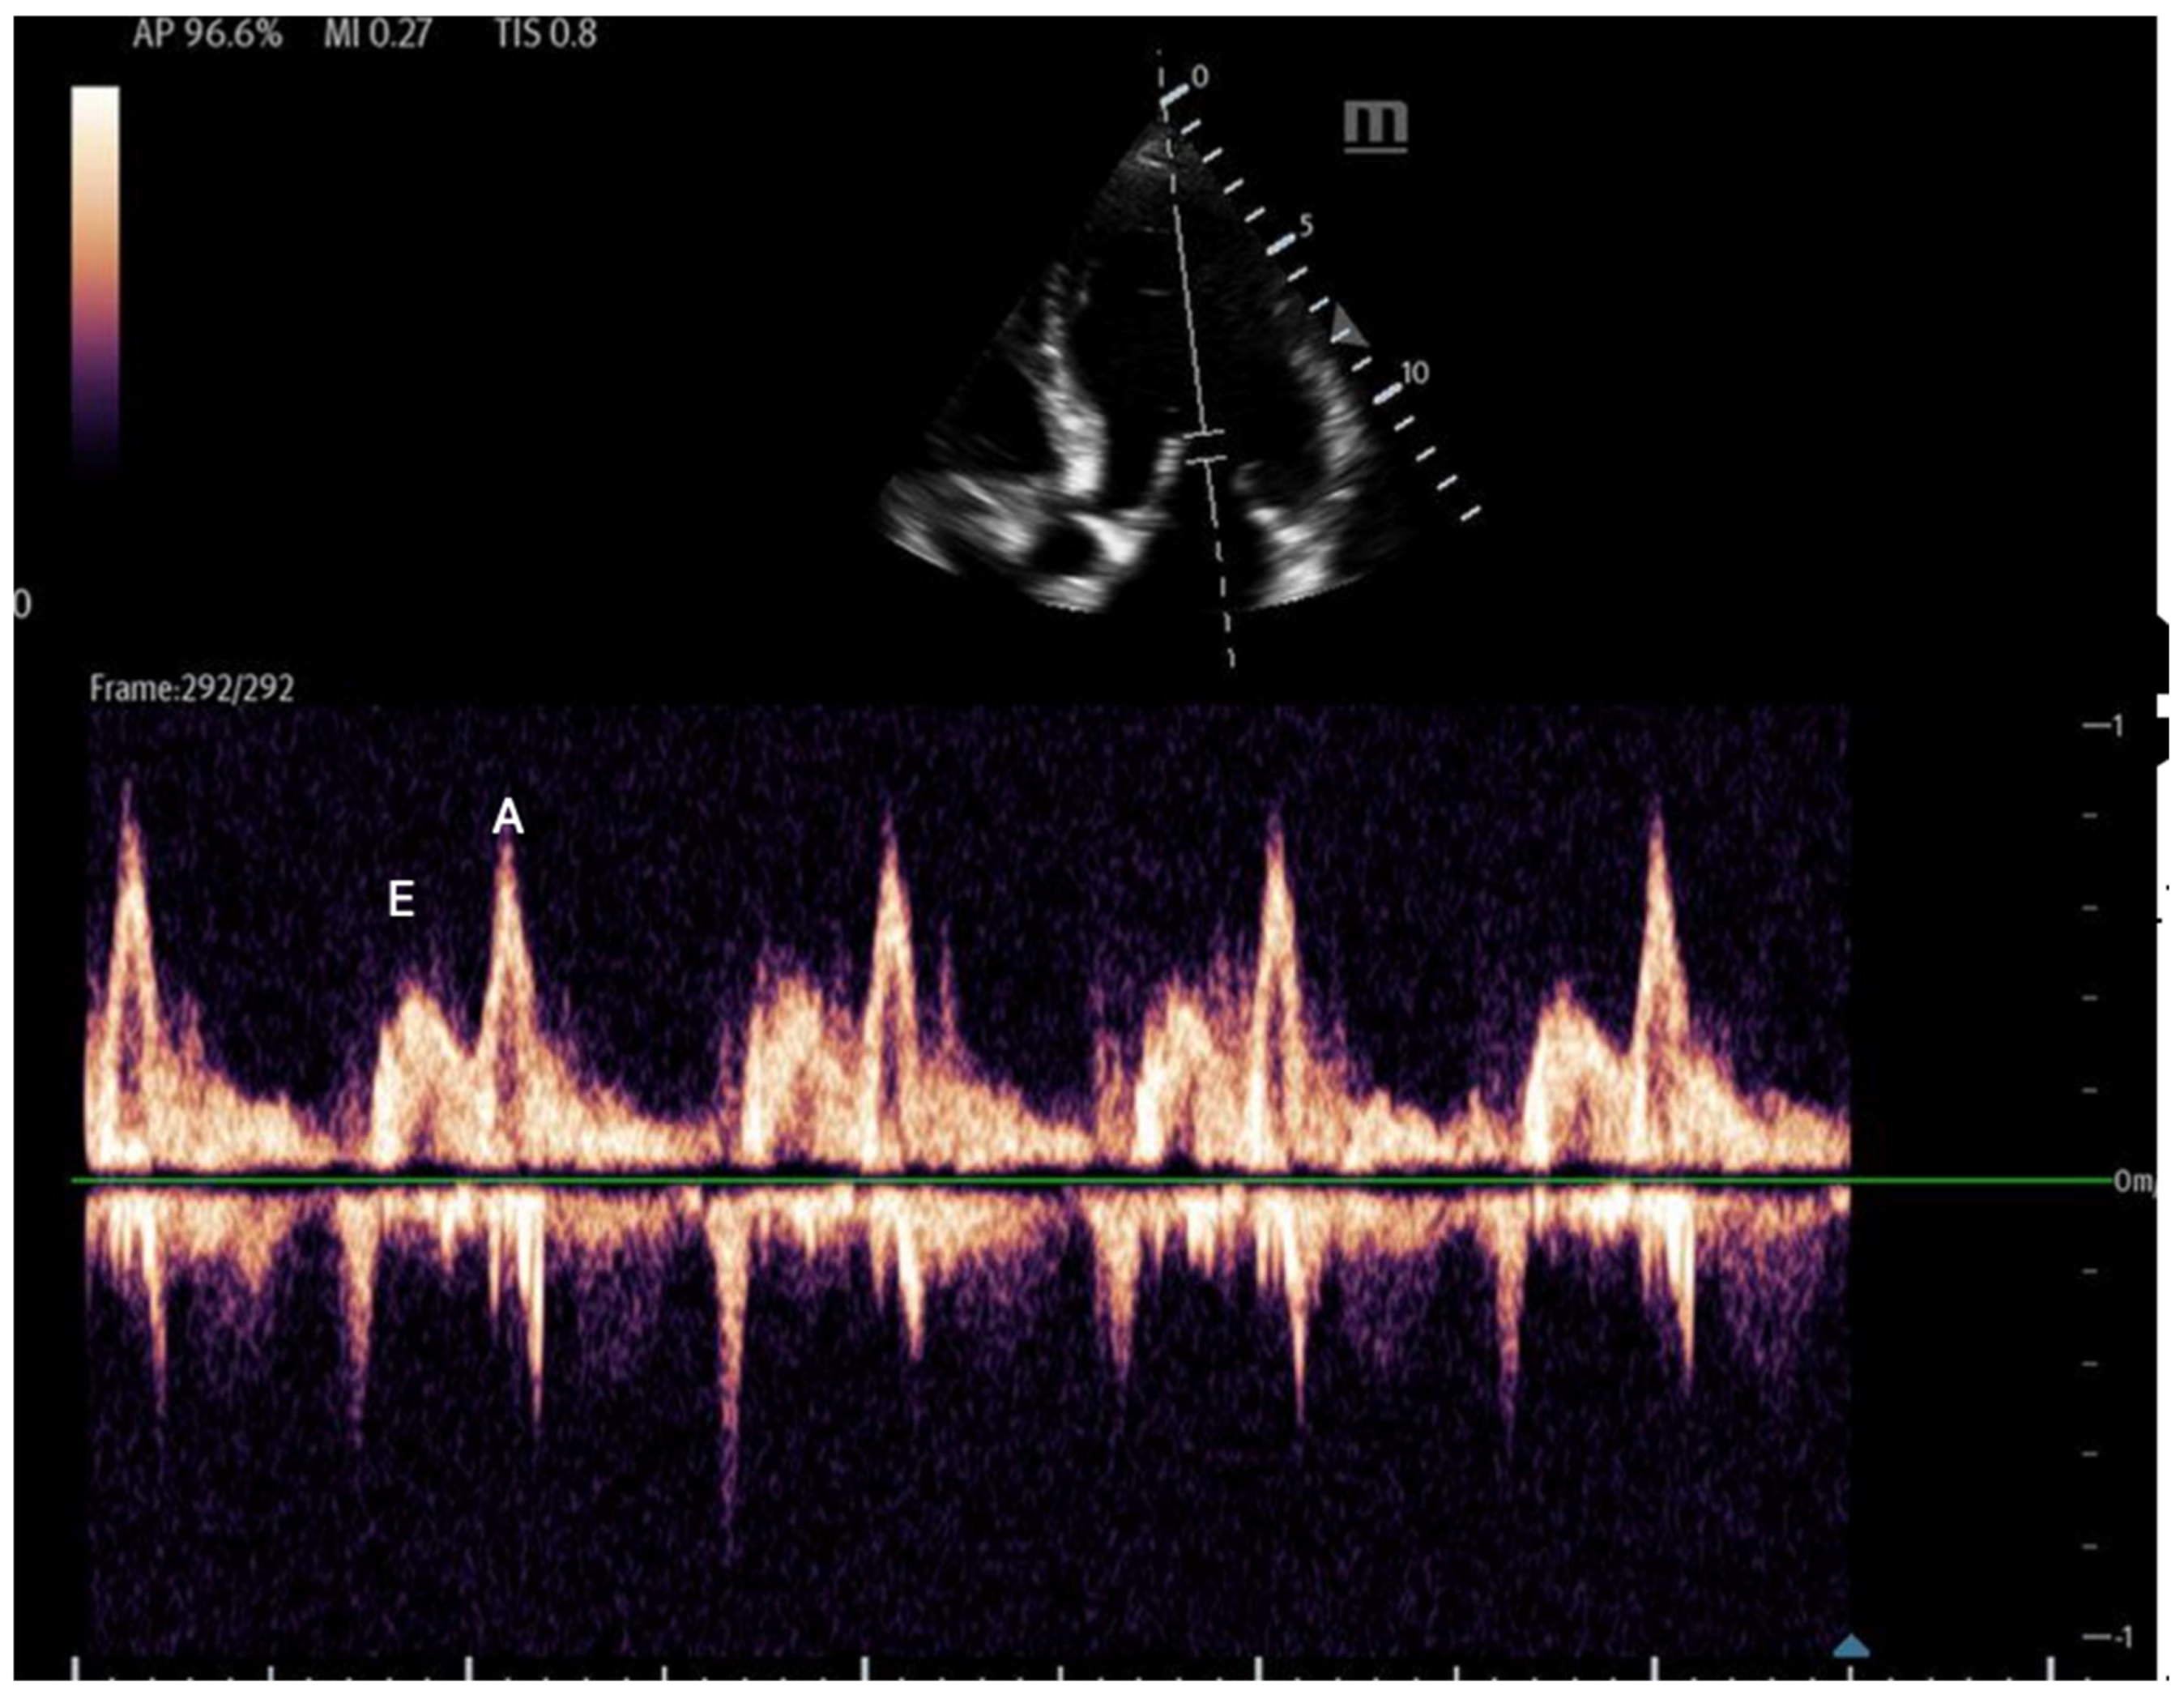

Left ventricular diastolic function:

Assessing left ventricular (LV) relaxation offers key insights into left-sided filling pressures, which can guide fluid and diuretic management based on the patient’s volume status. This evaluation also aids in distinguishing between pulmonary edema caused by elevated left atrial pressure (LAP) or primary lung disease. Imaging mitral inflow and myocardial tissue velocities allows the identification of abnormal relaxation patterns, with two commonly used point-of-care ultrasound measurements—mitral inflow and tissue Doppler—demonstrating 90% accuracy in diagnosing diastolic dysfunction in ICU patients [62].

- Mitral inflow: Assessed via pulsed-wave (PW) Doppler at the mitral valve tips in the apical four-chamber view, this measures the blood flow velocities entering the left ventricle as an upward deflection of the PW Doppler signal. The resultant E and A waves are then evaluated for their ratio (Figure 14).

Figure 14. Mitral inflow with PW Doppler gate at mitral valve tip (E and A waves). - Tissue Doppler: Measures myocardial movement during diastole using tissue Doppler at the septal annulus. The E/e′ ratio is calculated from the recorded e′ wave (Figure 15).